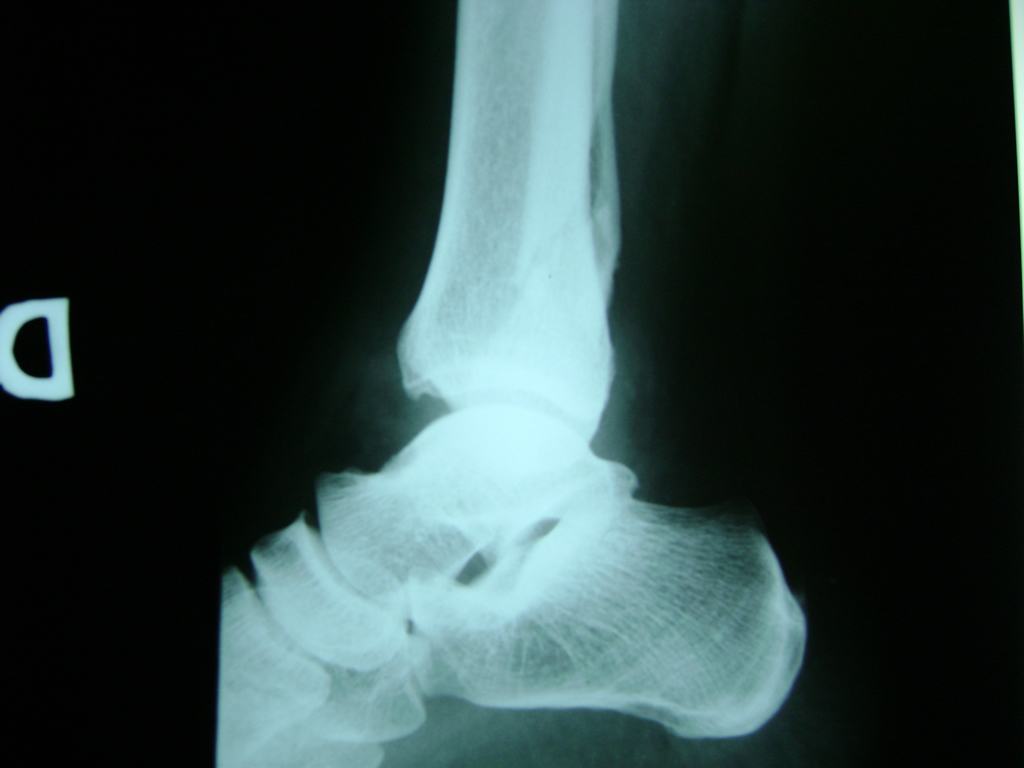

Una fractura de tobillo es la rotura de uno o más de los huesos del tobillo. Estas fracturas pueden ser:

- Parciales (el hueso está sólo parcialmente fisurado, no del todo).

- Completas (el hueso está perforado y está en 2 partes).

- Producirse en uno o ambos lados del tobillo.

Algunas fracturas de tobillo pueden requerir cirugía si:

- Los extremos de los huesos están desalineados entre sí (desplazados).

- La fractura se extiende hasta la articulación del tobillo (fractura intra-articular).

- Los tendones o ligamentos (tejidos que sujetan los músculos y los huesos entre sí) están rotos.

- El médico cree que sus huesos probablemente no sanen apropiadamente sin cirugía.

- El médico considera que la cirugía puede permitirle una recuperación más rápida y confiable.

- En los niños, la fractura involucra la parte del hueso del tobillo donde el hueso está creciendo.

Cuando se necesita cirugía, es probable que esta implique el uso de clavijas de metal, tornillos o placas para sostener los huesos en su lugar mientras la fractura se consolida. Los elementos de soporte pueden ser temporales o permanentes.